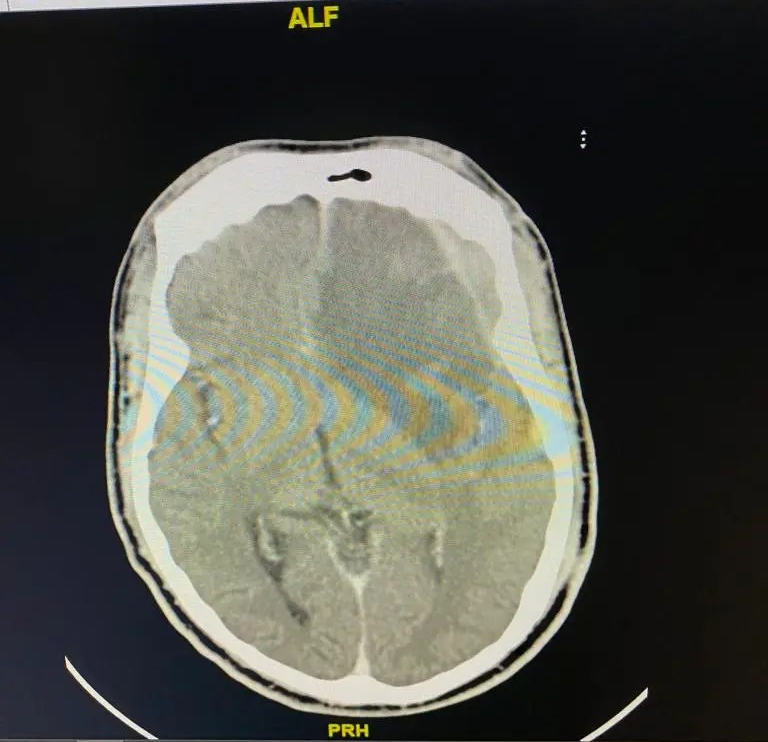

The work we do

S.T.D Neurosurgical Health Centre